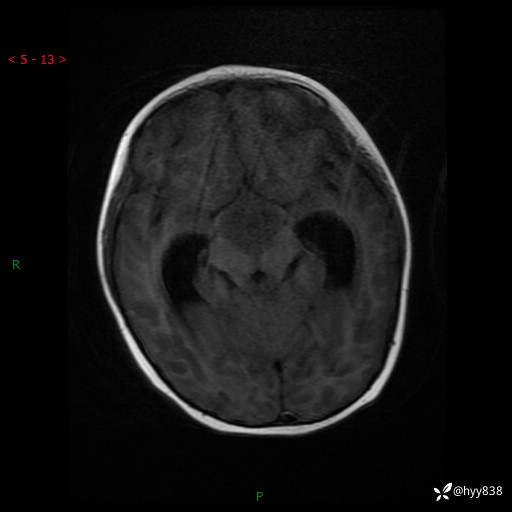

颅脑MRI平扫+增强

img